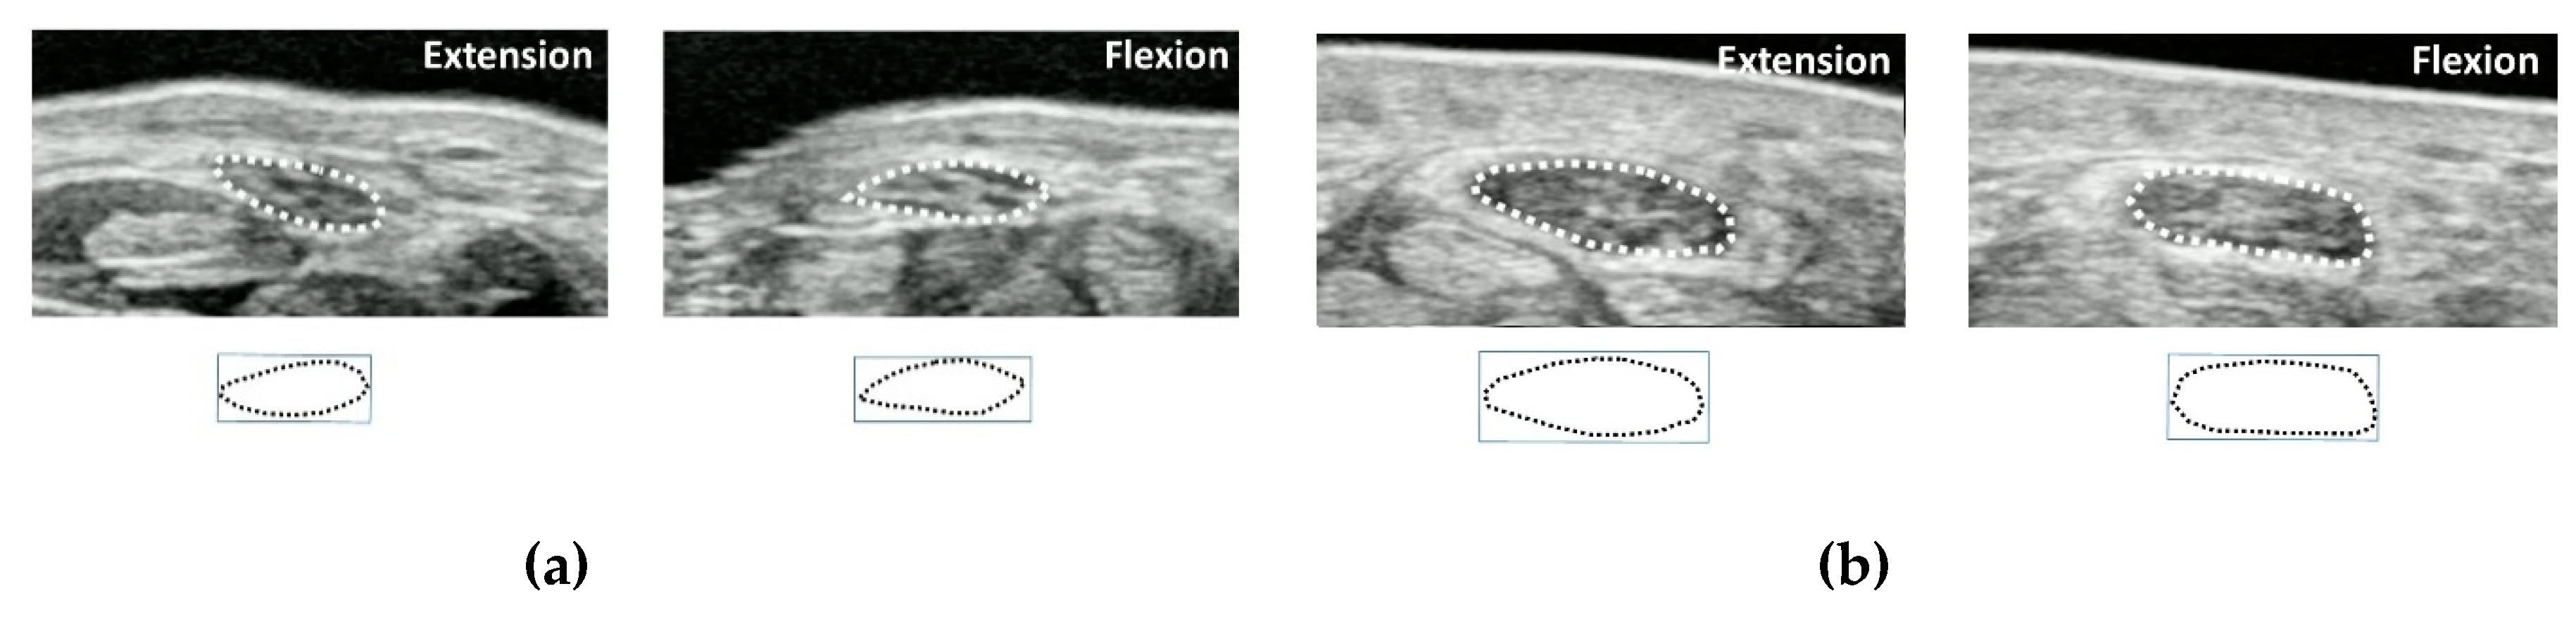

- Yoshii, Y.; Villarraga, H.R.; Henderson, J.; Zhao, C.; An, K.N.; Amadio, P.C. Ultrasound assessment of the displacement and deformation of the median nerve in the human carpal tunnel with active finger motion. J. Bone Joint Surg. Am. 2009, 91, 2922–2930. [Google Scholar] [CrossRef]

- Van Doesburg, M.H.; Henderson, J.; Yoshii, Y.; Mink van der Molen, A.B.; Cha, S.S.; An, K.N.; Amadio, P.C. Median nerve deformation in differential finger motions: Ultrasonographic comparison of carpal tunnel syndrome patients and healthy controls. J. Orthop. Res. 2012, 30, 643–648. [Google Scholar] [CrossRef]

- Yoshii, Y.; Ishii, T.; Tung, W.L.; Sakai, S.; Amadio, P.C. Median nerve deformation and displacement in the carpal tunnel during finger motion. J. Orthop. Res. 2013, 31, 1876–1880. [Google Scholar] [CrossRef]

- Yoshii, Y. Dynamic analysis of ultrasound image for the diagnosis of carpal tunnel syndrome. Kansetsugeka 2015, 34, 636–643. [Google Scholar]